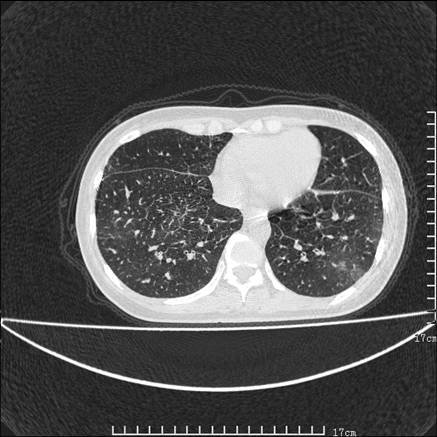

双肺小叶间增厚,双肺散布粟米影和磨玻璃状影,以双肺上叶为重。结合病史考虑转移(癌性淋巴细管炎)可能性大。

结合病史:认为是典型肺部癌性淋巴管炎、淋巴结转移。请看图解。

正如caihe主任所言,影像表现结合临床病史应该支持肺癌性淋巴管炎;上肺大片边缘不清的渗出病变,多系感染所致,临床有感冒病史并咳嗽表现。肺癌性淋巴管炎临床一般无咳嗽、咳痰症状。

支持 肺间质性肺炎,不除外癌性淋巴管炎,建议抗炎治疗复查---------小叶间隔增厚,磨玻璃影及片絮状影